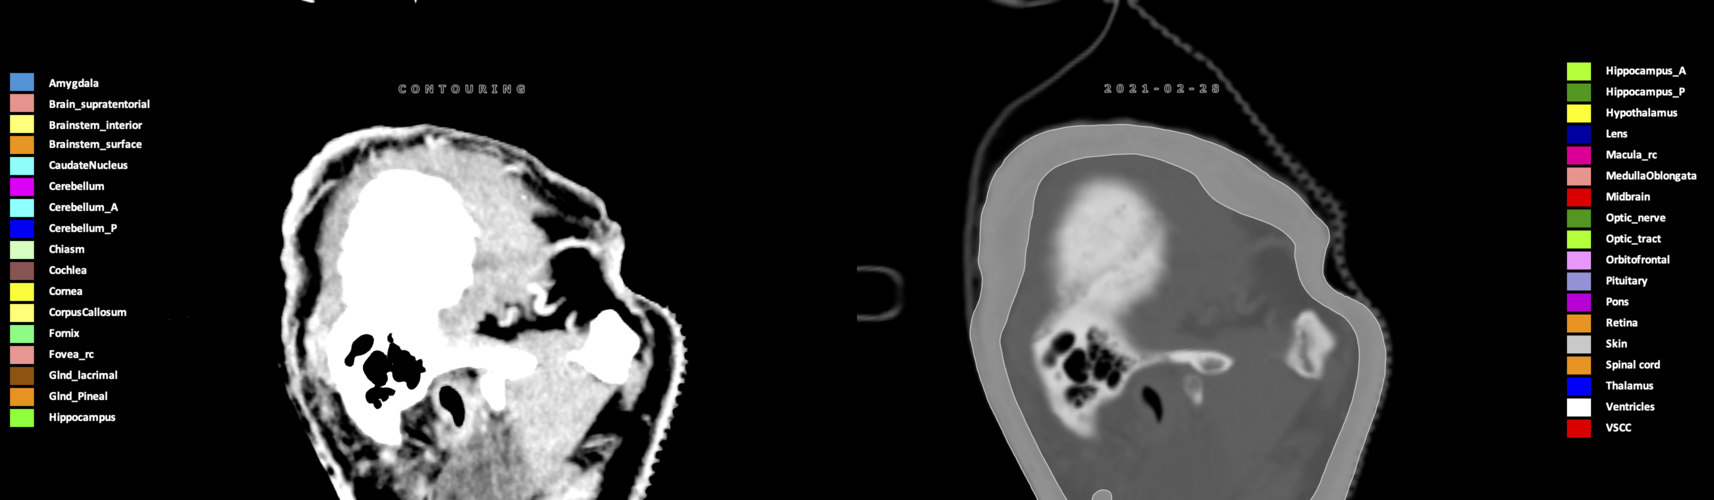

Eekers et al. have published an international neurological atlas for contouring of organs at risk in consensus with the European Particle Therapy Network (EPTN) in 2018 and an update in 2021. The purpose of this consensus atlas is to decrease inter- and intra-observer variability in delineating OARs relevant for neuro-oncology.

Included are all OARs known to be relevant for radiation-induced toxicity in neuro-oncology: brain, brainstem (midbrain, pons, medulla oblongata), chiasm, cerebellum (anterior & posterior), cochlea, cornea, hippocampus (anterior & posterior), hypothalamus, lens, lacrimal gland, optic nerve, pituitary, skin, and vestibular & semicircular canals. To further facilitate research on cognition, vision and radiological changes after irradiation of the brain, potential clinically-relevant OARs are included: amygdala, caudate nucleus, cerebellum (anterior & posterior), corpus callosum, fornix, macula, optic tract, orbitofrontal cortex, periventricular space (PVS), pineal gland, and thalamus.

Three-dimensional delineation of the 25 consensus OARs for neuro-oncology are shown on CT (WW/WL 120/40, 3000/600), 3T MR images, (T1Gd, T2FLAIR 1mm) and 7T MR (MP2RAGE 0.7 mm). All are presented in transversal, sagittal and coronal view.